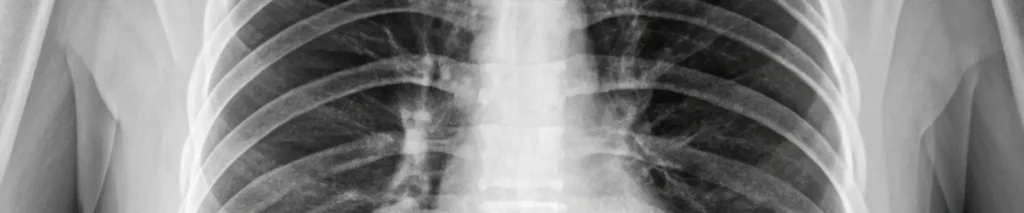

Poucos pais já ouviram falar em cirurgia pediátrica torácica, mas ela é fundamental para tratar doenças que afetam os pulmões e as vias respiratórias de crianças.

É uma área da cirurgia pediátrica que se dedica a tratar condições que envolvem o tórax, os pulmões, a traqueia e os brônquios. Esses órgãos são responsáveis pela respiração e precisam de cuidados muito delicados durante a infância.

Essas cirurgias exigem habilidade altamente especializada, já que o tórax de uma criança é muito diferente do de um adulto. Além disso, a recuperação, o controle da dor e o acompanhamento do crescimento precisam ser pensados de forma única.